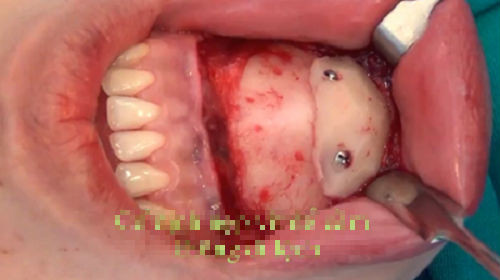

Độn cằm: Phẫu thuật độn cằm được biết đến là cách để có được một chiếc cằm nhọn, dài, thon gọn và hài hòa hơn. Độn cằm được thực hiện bằng cách rạch phần thịt ở dưới cằm và đưa phần độn vào lắp ráp bên trong. Nó có liên quan trực tiếp tới các phần quan trọng trên gương mặt, vì thế có thể dễ dàng xảy ra nguy hiểm.

Không chỉ có những nguy hiểm và biến chứng dễ xảy ra, chúng ta còn phải đối mặt với tình trạng cằm bị biến dạng sau khi phẫu thuật. Các biến chứng trên gương mặt thường gặp do độn cằm là cằm bị lệch, cằm nhọn bất thường, thiếu tự nhiên, cằm bị biến dạng…